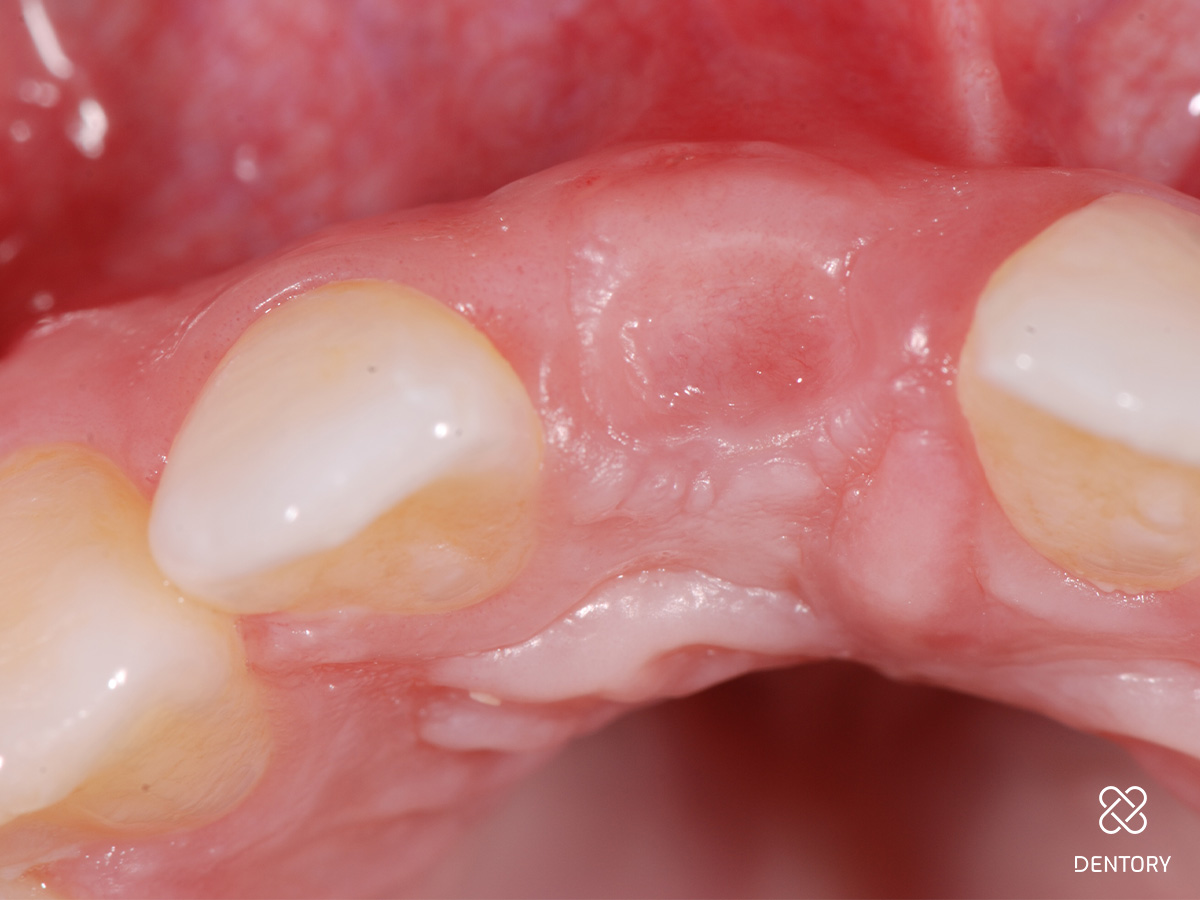

Abbildung 5

Sondieren der bukkalen Knochenstrukturen mittels Biotyp-Sonde; im Bereich der Resorption kam es zum lokalen Verlust der vestibulären Lamelle.